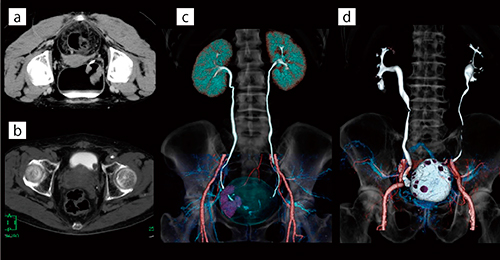

膀胱の腫瘍性病変においては,臨床科より,腫瘍と尿管の位置関係を明確に表した画像を求められている。そのため,排泄相の撮影を追加し,尿管を描出する場合がある。以前は膀胱内にオリーブオイルを注入し撮影を行っていたが,注入を行う時間のロスや,病変部が膀胱後壁に存在する場合は腹臥位撮影の必要があり(図1 a),患者も尿意が強くなるため排泄相までの撮影は困難であった。また,膀胱内にオリーブオイル,尿,造影剤と3層のニボーを形成するため(図1 a),VR画像作成時に膀胱のレイヤーを抽出するにはMPR画像上にてセミオート抽出のフリーハンドモードで行う必要があった(図1 c)。

そこで現在は,ある程度尿をためた状態で通常の造影撮影を実施し,次の患者の検査を行った後に再入室してもらい,排泄相のみの追加撮影を行っている。これにより注入時間のロスは軽減し,膀胱内の造影剤が歩行により尿と均一に混ざることによって,病変部の位置に関係なく常に背臥位で撮影を行うことができる(図1 b)。また,膀胱のレイヤー抽出においても,オパシティカーブの調整のみと格段に容易になった(図1 d)。本法は患者が一度退室するため,画像処理において早期相(図2 a),遅延相(図2 b),排泄相(図2 c)の寝台位置が一致しない(図2 d)。そこで,各フェーズの骨のレイヤーをマルチボリューム処理上でメルクマールとし,マニュアルのボリューム操作で位置合わせを行っている。これにより,患者やわれわれ診療放射線技師の負担を軽減しながらも,オリーブオイル以上の効果を得ることが可能となった(図2 e)。

図1 膀胱腫瘍におけるオリーブオイル膀胱注入あり,注入なしのCT画像

a:オリーブオイルを膀胱に注入した排泄相アキシャル画像。腫瘍周囲をオリーブオイルで満たすため腹臥位にて撮影。

b:オリーブオイルを注入していない排泄相アキシャル画像。背臥位撮影において膀胱全体が造影剤で満たされている。

c:オリーブオイルを膀胱に注入した早期相,遅延相,排泄相のマルチボ リューム処理VR画像。

d:オリーブオイルを膀胱に注入していない早期相,遅延相,排泄相のマルチボリューム処理VR画像。